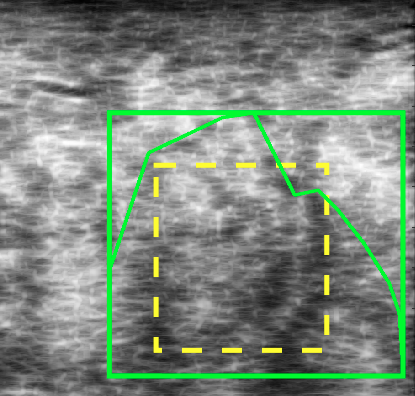

In [15], only “global” barcodes were used, meaning that one barcode was extracted for the entire image. But it was recognized that using “local” barcodes may be of more significance when dealing with specific regions of interest (ROIs) (see Fig. 2). In this research, the two were combined and every image was tagged with two barcodes. The “global” barcode captures the general appearance of the image, and the “local” (or ROI-based) barcode captures the texture and intensity variations of the tumour.

Assuming that there is a set of training images along with their ground-truth segments, we propose to use barcodes in order to estimate the location of a bounding box around the tumour (contoured by the expert as a ground-truth) with starting coordinates and ending coordinates (Fig. 4). Two barcodes were assigned to each bounding box: a global barcode for the entire image, and a local barcode for the bounding box (Fig. 5). The rough localization of a bounding box for the tumour can be formulated as a search problem: given a database consisting of training images with their corresponding bounding boxes , and global and ROI Radon barcodes , the bounding box was formulated for a query image by first finding the top similar images in the database via Hamming distance between corresponding barcodes: